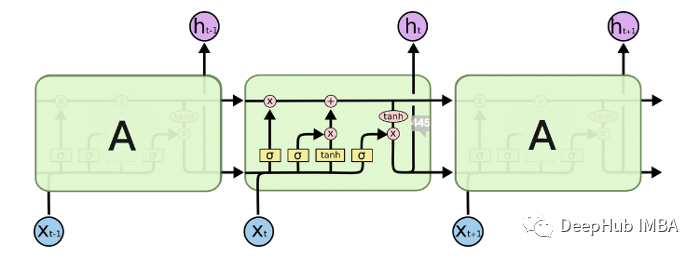

LSTM

简单的RNN不能很好地处理长期依赖关系。lstm被明确设计为避免长期依赖问题。

lstm有三个输入和两个输出,能够向单元状态中删除或添加信息,也可以不加修改地传递信息。

注意力机制

注意力模型也称为注意力机制,是一种深度学习技术,用于提供对特定组件的额外关注。注意力模型的目的是将更大、更复杂的任务简化为更小、更易于管理的注意力区域,以便按顺序理解和处理。

注意力模型的最初目的是帮助改善计算机视觉和基于编码器-解码器的神经机器翻译系统。该系统使用自然语言处理 (NLP) 并依赖于具有复杂功能的庞大数据库。使用注意力模型有助于创建固定长度向量的映射以生成翻译和理解。

本文中我们将使用 Bahdanau 和 Loung 建议的论文中使用全局注意力模型(Global Attention Model)。

该模型基于与源位置和先前生成的目标词相关联的上下文向量来预测目标词。具有注意机制的Seq2Seq模型由编码器、解码器和注意层组成。